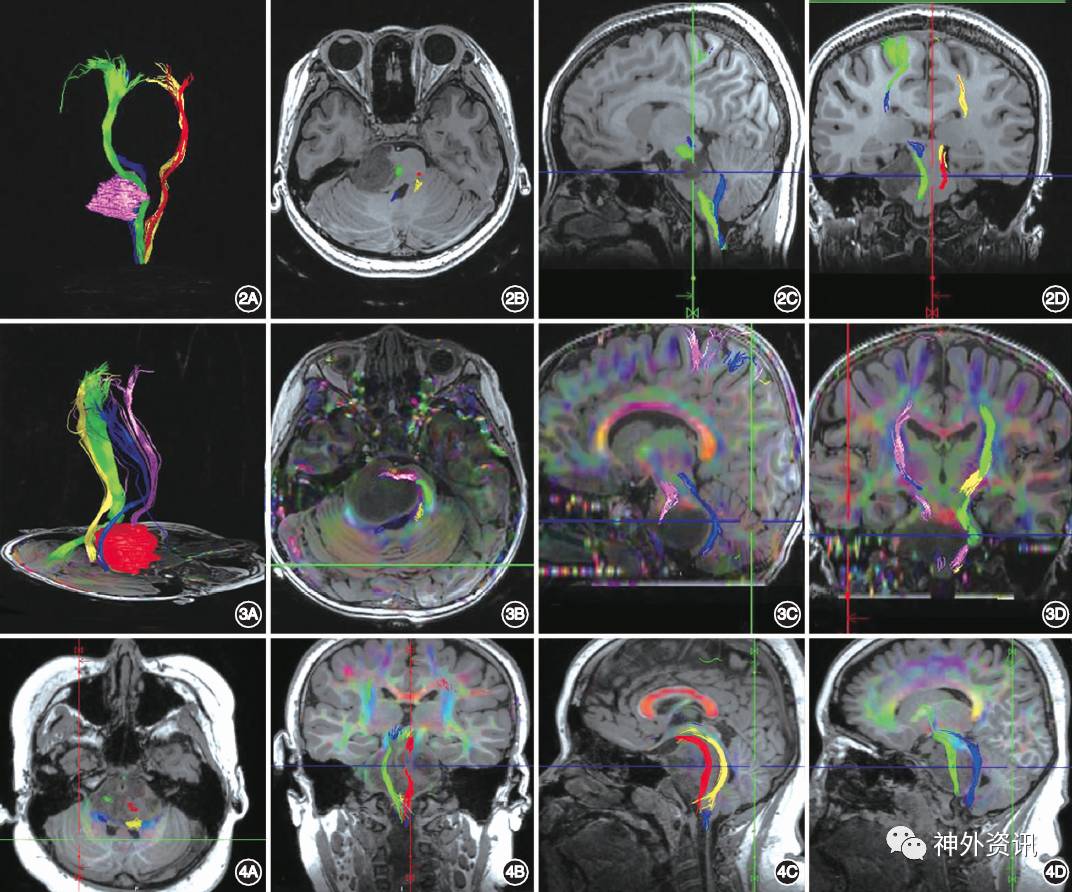

二、根据DTI成像中皮质脊髓束(corticospinal tract, CST)和肿瘤的位置关系将BSG分为3型

A型:为推挤型,CST受到肿瘤推挤发生移位,患者四肢肌力为Ⅳ~Ⅴ级(图2)。

B型:为推挤+破坏型,CST同时受到肿瘤的推挤和破坏,患者受累肢体肌力为Ⅱ~Ⅲ级(图3)。

C型:为穿过型,CST从肿瘤内部穿过,患者受累肢体肌力为Ⅲ~Ⅴ级(图4)。

图2. DTI分型A型:肿瘤单纯推挤CST(推挤型)A.纤维束和肿瘤的三维重建结果,绿色为右侧的CST,肿瘤将CST推向左侧,患者的左侧肢体肌力为V-级;B-D.分别为磁共振T1WI轴位、矢状位以及冠状位与纤维束的融合图像,绿色为右侧的CST,红色为左侧的CST。

图3. DTI分型B型:肿瘤推挤并破坏CST(推挤-破坏型)A.纤维束和肿瘤的三维重建结果,粉红色为右侧的CST,可见CST明显受到肿瘤推挤发生移位,同时患者左侧肢体肌力为III级;B-D.分别为磁共振T1WI轴位、矢状位和冠状位与纤维束的融合图像,粉红色为右侧的CST。

图4. DTI分型C型:DTI穿过肿瘤(穿过型),红色和绿色分别表示左侧和右侧CST A,B.分别为磁共振T1WI轴位和冠状位,显示双侧CST均从肿瘤内部穿过;C,D.磁共振T1WI矢状位,分别显示在肿瘤内部穿行的左侧和右侧的CST(DTI为弥散张量成像,CST为皮质脊髓束)。

DTI成像所显示的纤维束是在数学模型基础上后期重建所获得的,纤维束形态和数量受图像采集和重建参数的影响较大。由于目前尚缺乏统一的技术标准,所以建议DTI作为制定手术入路的辅助性参考依据,术中应用可与电生理监测相结合。推荐应用3.0 T MRI进行数据采集,采集图像时患者应保持头部静止,儿童患者无法配合时,建议在采集图像前30 min给予水合氯醛诱导睡眠。